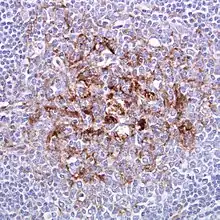

| Biopsy of the tonsil in variant CJD. Prion protein immunostaining. | |

Examination of brain tissue is required to confirm a diagnosis of variant CJD.[2] The following confirmatory features should be present:[2]

- Numerous widespread kuru-type amyloid plaques surrounded by vacuoles in both the cerebellum and cerebrum – florid plaques.[2]

- Spongiform change and extensive prion protein deposition shown by immunohistochemistry throughout the cerebellum and cerebrum.[2]